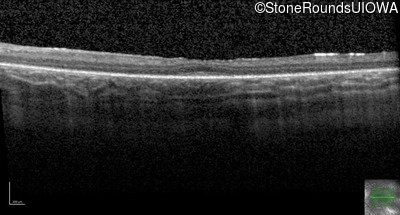

OD OS

Age at visit: 10 years

Age at visit: 11 years

Age at visit: 12 years

Age at visit: 13 years

Age at visit: 14 years

Age at visit: 16 years